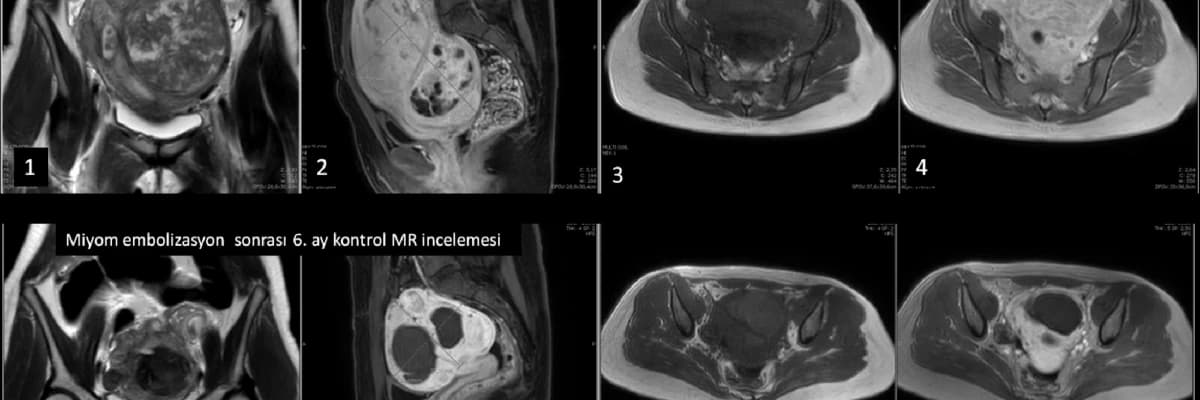

Miyom tedavisinde girişimsel radyoloji önemli bir rol oynamaktadır. Uzun yıllardan beri embolizasyon güvenilir bir miyom tedavi yöntemi olarak uygulanmaktadır. Embolizasyondan sonra hamile kalan ve normal doğum yapan bir çok kadın bildirilmiştir. Dolayısıyla, miyom embolizasyon tedavisinin genel olarak gebe kalmaya ve sağlıklı doğum yapmaya bir engel oluşturmadığı gösterilmiştir. Ancak embolizasyon işlemi sırasında çok düşük olasılık olsa da yumurtalıklara ve rahime kalıcı hasar verme riski mevcuttur. Bu konuda halen devam eden bir çok bilimsel çalışma yapılmaktadır. Özellikle miyom embolizasyon ve miyomektomi sonrası hamilelik oranları bir çok çalışmada karşılaştırılmıştır. Bazı çalışmalarda miyomektomi sonrası hamilelik oranları bir miktar daha yüksek bildirilmiş olsa da sonuçlar arasında ciddi sapmalar mevcuttur. Miyom embolizasyonu sonrası hamilelik oranları miyomektomiye yakın olarak bulunan çalışmalar da bildirilmiştir.

Güncel bilgilerimize göre, gelecekte mutlaka gebelik isteyen ve tekli miyomlara sahip genç kadınlarda, miyom tedavisi için ilk seçenek miyomektomi olsa da cerrahi istemeyen hastalarda miyom embolizasyonu önemli bir alternatiftir. Gebeliği mutlak koşul olarak görmeyen hastalarda ya da miyomektomiye uygun olmayan çok sayıda miyom içeren hastalarda embolizasyon tedavisi öncelikle tercih edilmelidir.